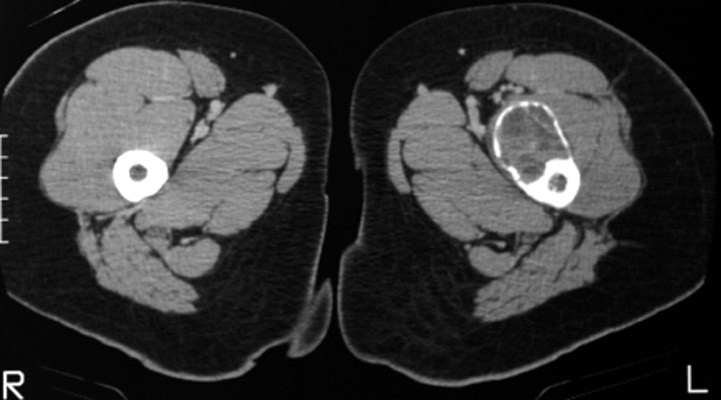

Frontal radiograph of the right hip and CT scan of the hips on a different patient. Both reveal a cystic bubbly lesion with fine internal septations. Additionally, compromise of the cortical margin of the lesion is present as well. The "blister of bone" sign refers to a bubbly cystic lesion with a saccular protrusion of the cortex with multiple fine internal septae. The shell of the lesion may fracture resulting in extravasation of blood into the adjacent tissues. This sign is highly characteristic of aneurysmal bone cyst.

AP hip - Click on the image for a larger versionA - Click on the image for a larger versionB